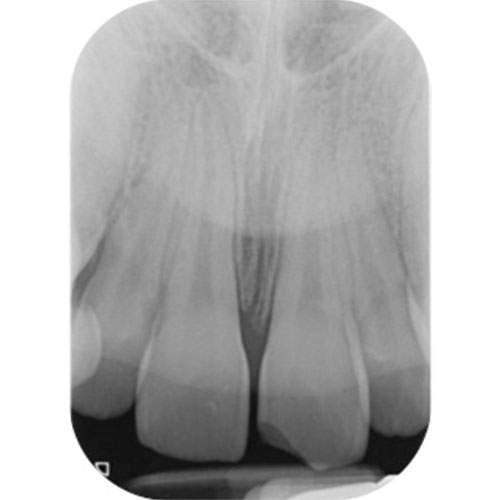

Radiograph: Periapical radiograph of the UL1 showing normal periodontal ligament outline.

Radiographic findings

A radiograph of a tooth with an isolated enamel fracture will appear normal